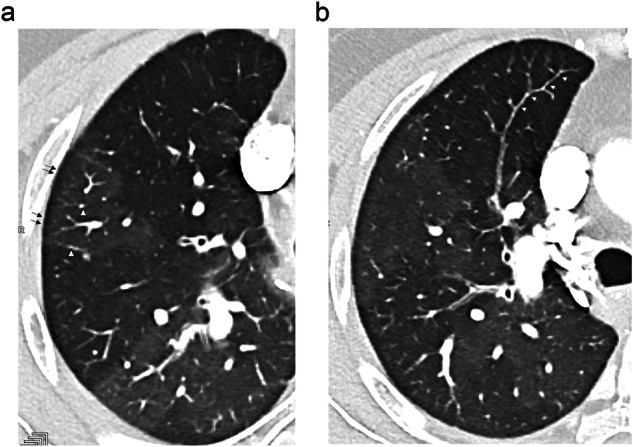

目的:探讨慢性血栓栓塞性肺动脉高压(CTEPH)患者肺微血管病变的CT表现。材料与方法:对29例患者进行高空间分辨率光子计数检测器(PCD)-CT扫描。每位患者最多选择三对,每对由马赛克灌注的高衰减区和低衰减区组成。结果:86对病例的对比分析表明:(a)低衰减区微结节不清晰(p = 0.008)、小叶磨玻璃混浊(p = 0.01)和模糊(p = 0.003)的发生率较高;(b)新生血管频率无显著差异(p = 0.43)。在22例中枢性和外周性CTEPH患者的66对研究中,在低衰减区观察到类似的趋势;在7例外周性CTEPH患者的20对患者中,发现微结节不清晰、小叶磨玻璃样混浊、高衰减区模糊。平均肺动脉压≤42 mmHg(即平均肺动脉压中位数)的患者有45对,显示微结节定义不清(p = 0.003)和模糊(p 42 mmHg)的频率更高。结论:提示微血管病变的CT表现多出现在低灌注区,严重ph患者的CT表现有均匀化的趋势。关键点:肺微血管病变在血栓动脉内膜切除术成功后残余肺动脉高压的起源中起着至关重要的作用,目前超出了影像学的范围。发现CTEPH在远端肺循环水平的形态学异常在马赛克灌注的各个区都有表现。本研究提示,PCD-CT的高空间分辨率具有接近CTEPH小血管病变复杂病理生理的能力,为治疗决策提供重要信息。

Purpose: To evaluate CT findings suggestive of lung microvasculopathy in patients with chronic thromboembolic pulmonary hypertension (CTEPH).

Materials and methods: Twenty-nine patients were scanned with high-spatial resolution on a photon-counting detector (PCD)-CT unit. A maximum of three pairs per patient, each composed of hyper- and hypo-attenuating areas of mosaic perfusion, were selected.

Results: Comparative analysis of the 86 selected pairs showed: (a) a higher frequency of ill-defined micronodules (p = 0.008), lobular ground-glass opacities (p = 0.01) and haziness (p = 0.003) in hypoattenuated areas; (b) there was no significant difference in the frequency of neovascularity (p = 0.43). Similar trends were observed in hypoattenuating areas of the 66 pairs studied in the 22 patients with central and peripheral CTEPH; an absence of ill-defined micronodules, lobular ground-glass opacities, and haziness in hyperattenuating areas was noticed in the 20 pairs studied in the 7 patients with peripheral CTEPH. Patients with a mean pulmonary artery pressure ≤ 42 mmHg (i.e., the median value of mean pulmonary artery pressure) had 45 pairs compared, showing a higher frequency of ill-defined micronodules (p = 0.003) and haziness (p < 0.001) in hypoattenuated areas, together with a higher frequency of subpleural systemic-to-pulmonary anastomoses (p = 0.02). There were no statistical differences in the frequency of CT findings between hypo- and hyper-attenuating areas in the 41 pairs of patients with a mean pulmonary artery pressure > 42 mm Hg.

Conclusion: CT features suggestive of microvasculopathy were more frequent in areas of hypoperfusion, with a trend toward homogenization of CT findings in patients with severe PH.

Key points: Question Lung microvascular lesions play a crucial role in the origin of residual pulmonary hypertension after successful thromboendarterectomy, currently beyond the scope of imaging. Findings The expected morphological abnormalities at the level of distal pulmonary circulation in CTEPH were found to be depictable in each zone of mosaic perfusion. Clinical relevance This study suggests that the high-spatial resolution of PCD-CT has the capability of approaching the complex pathophysiology of small-vessel disease in CTEPH, providing important information prior to therapeutic decisions.